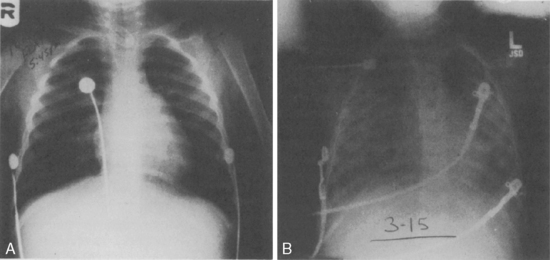

Late diagnosis can result in respiratory difficulties ranging from life-threatening airway obstruction to chronic wheezing and cough. The diagnosis of recurrent pneumonia may actually represent inflammation around the foreign body.215 Misdiagnosis and mismanagement of FBA increases the duration of symptoms, rate of complications, and cost prior to correct diagnosis.143 Complications from delayed diagnosis include granulation tissue formation surrounding the foreign body, persistent fever, reactive airways disease, or recurrent pneumonia. Diagnosis and removal become more challenging in these patients.248 Initial diagnostic testing includes anteroposterior and lateral chest radiographs. Radiographic evaluation can confirm FBA but cannot rule it out.117 Metallic objects will be visible on the chest radiograph; however, objects such as peanuts or plastics usually are not seen. Radiopaque FBA findings have been reported in approximately 20% of patients.248

When a single foreign body is lodged in a single bronchus, unilateral obstructive emphysema can be present on a chest radiograph and may be identified more readily if films are taken at both inspiration and expiration (Fig. 9-18), including anteroposterior and decubitus films. Paired inspiratory and expiratory films are often difficult to obtain in children who are unable to cooperate.248 Chest fluoroscopy may be considered in patients with normal radiographs but a strong history consistent with FBA. Fluoroscopy often reveals air trapping and an inspiratory shift of the mediastinum to the side contralateral to the foreign body.248

image

Fig. 9-18 Foreign body aspiration. The child in shown A, B, and C aspirated a peanut. The child shown D and E aspirated a small tack. A, Because the aspirated substance is not radiopaque, the diagnosis must be made on the basis of clinical examination and evidence of air trapping on radiographic examination. This posterior-anterior view is relatively normal in appearance. Hyperinflation is not obvious, so decubitus films were obtained. B, This left lateral decubitus film (obtained with the patient's left side down) demonstrates normal compression of the left lung in this position. The left diaphragm is elevated, and the mediastinum moves into the left chest. The left lung appears to be more vascular because it is compressed. C, This right lateral decubitus film is diagnostic of the right mainstem bronchus obstruction. Despite the fact that the right lung is in a dependent position, there is no evidence of right lung compression, and no mediastinal shift into the right chest. The right lung is hyperinflated, which is suggestive of bronchial obstruction. D, The tack was aspirated as this young boy attempted to use a homemade blow-gun. The radiopaque tack is visible in the right chest and appears to be in the right mainstem bronchus. E, The lateral view of the same patient as in D confirms the presence of the tack in the right bronchus.

(Chest radiographs courtesy Sharon Stein and John Pietsch, Vanderbilt University Medical Center, Nashville, TN.)